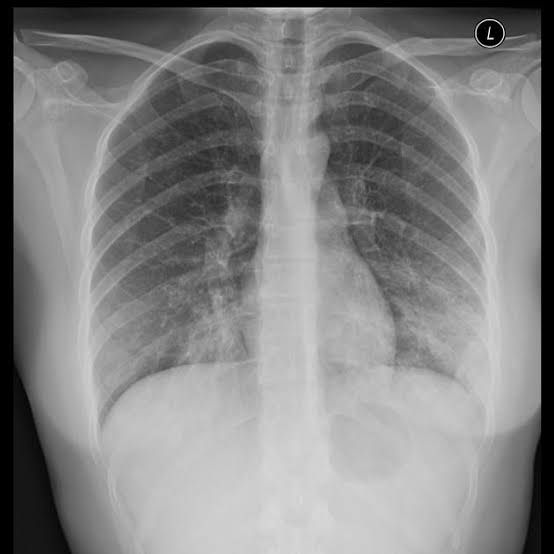

Can anyone help me visually differentiate between these two X-rays like I can see they are different but what's the terminology for them and also causative organism? #NEETpg #Inicet